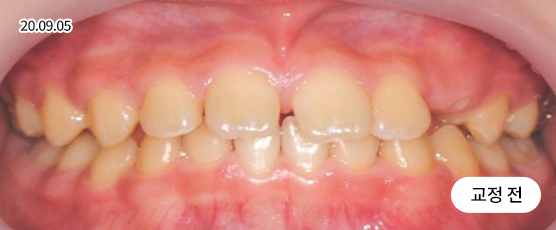

덧니교정 Solution

덧니는 악궁 크기, 얼굴형, 골격 등을 고려해 발치, 비발치를 현명하게 판단하여 치료합니다.

치아가 정렬될 공간을 확보하기 위해, 경우에 따라 소구치(작은 어금니)를 발치할 수 있습니다.